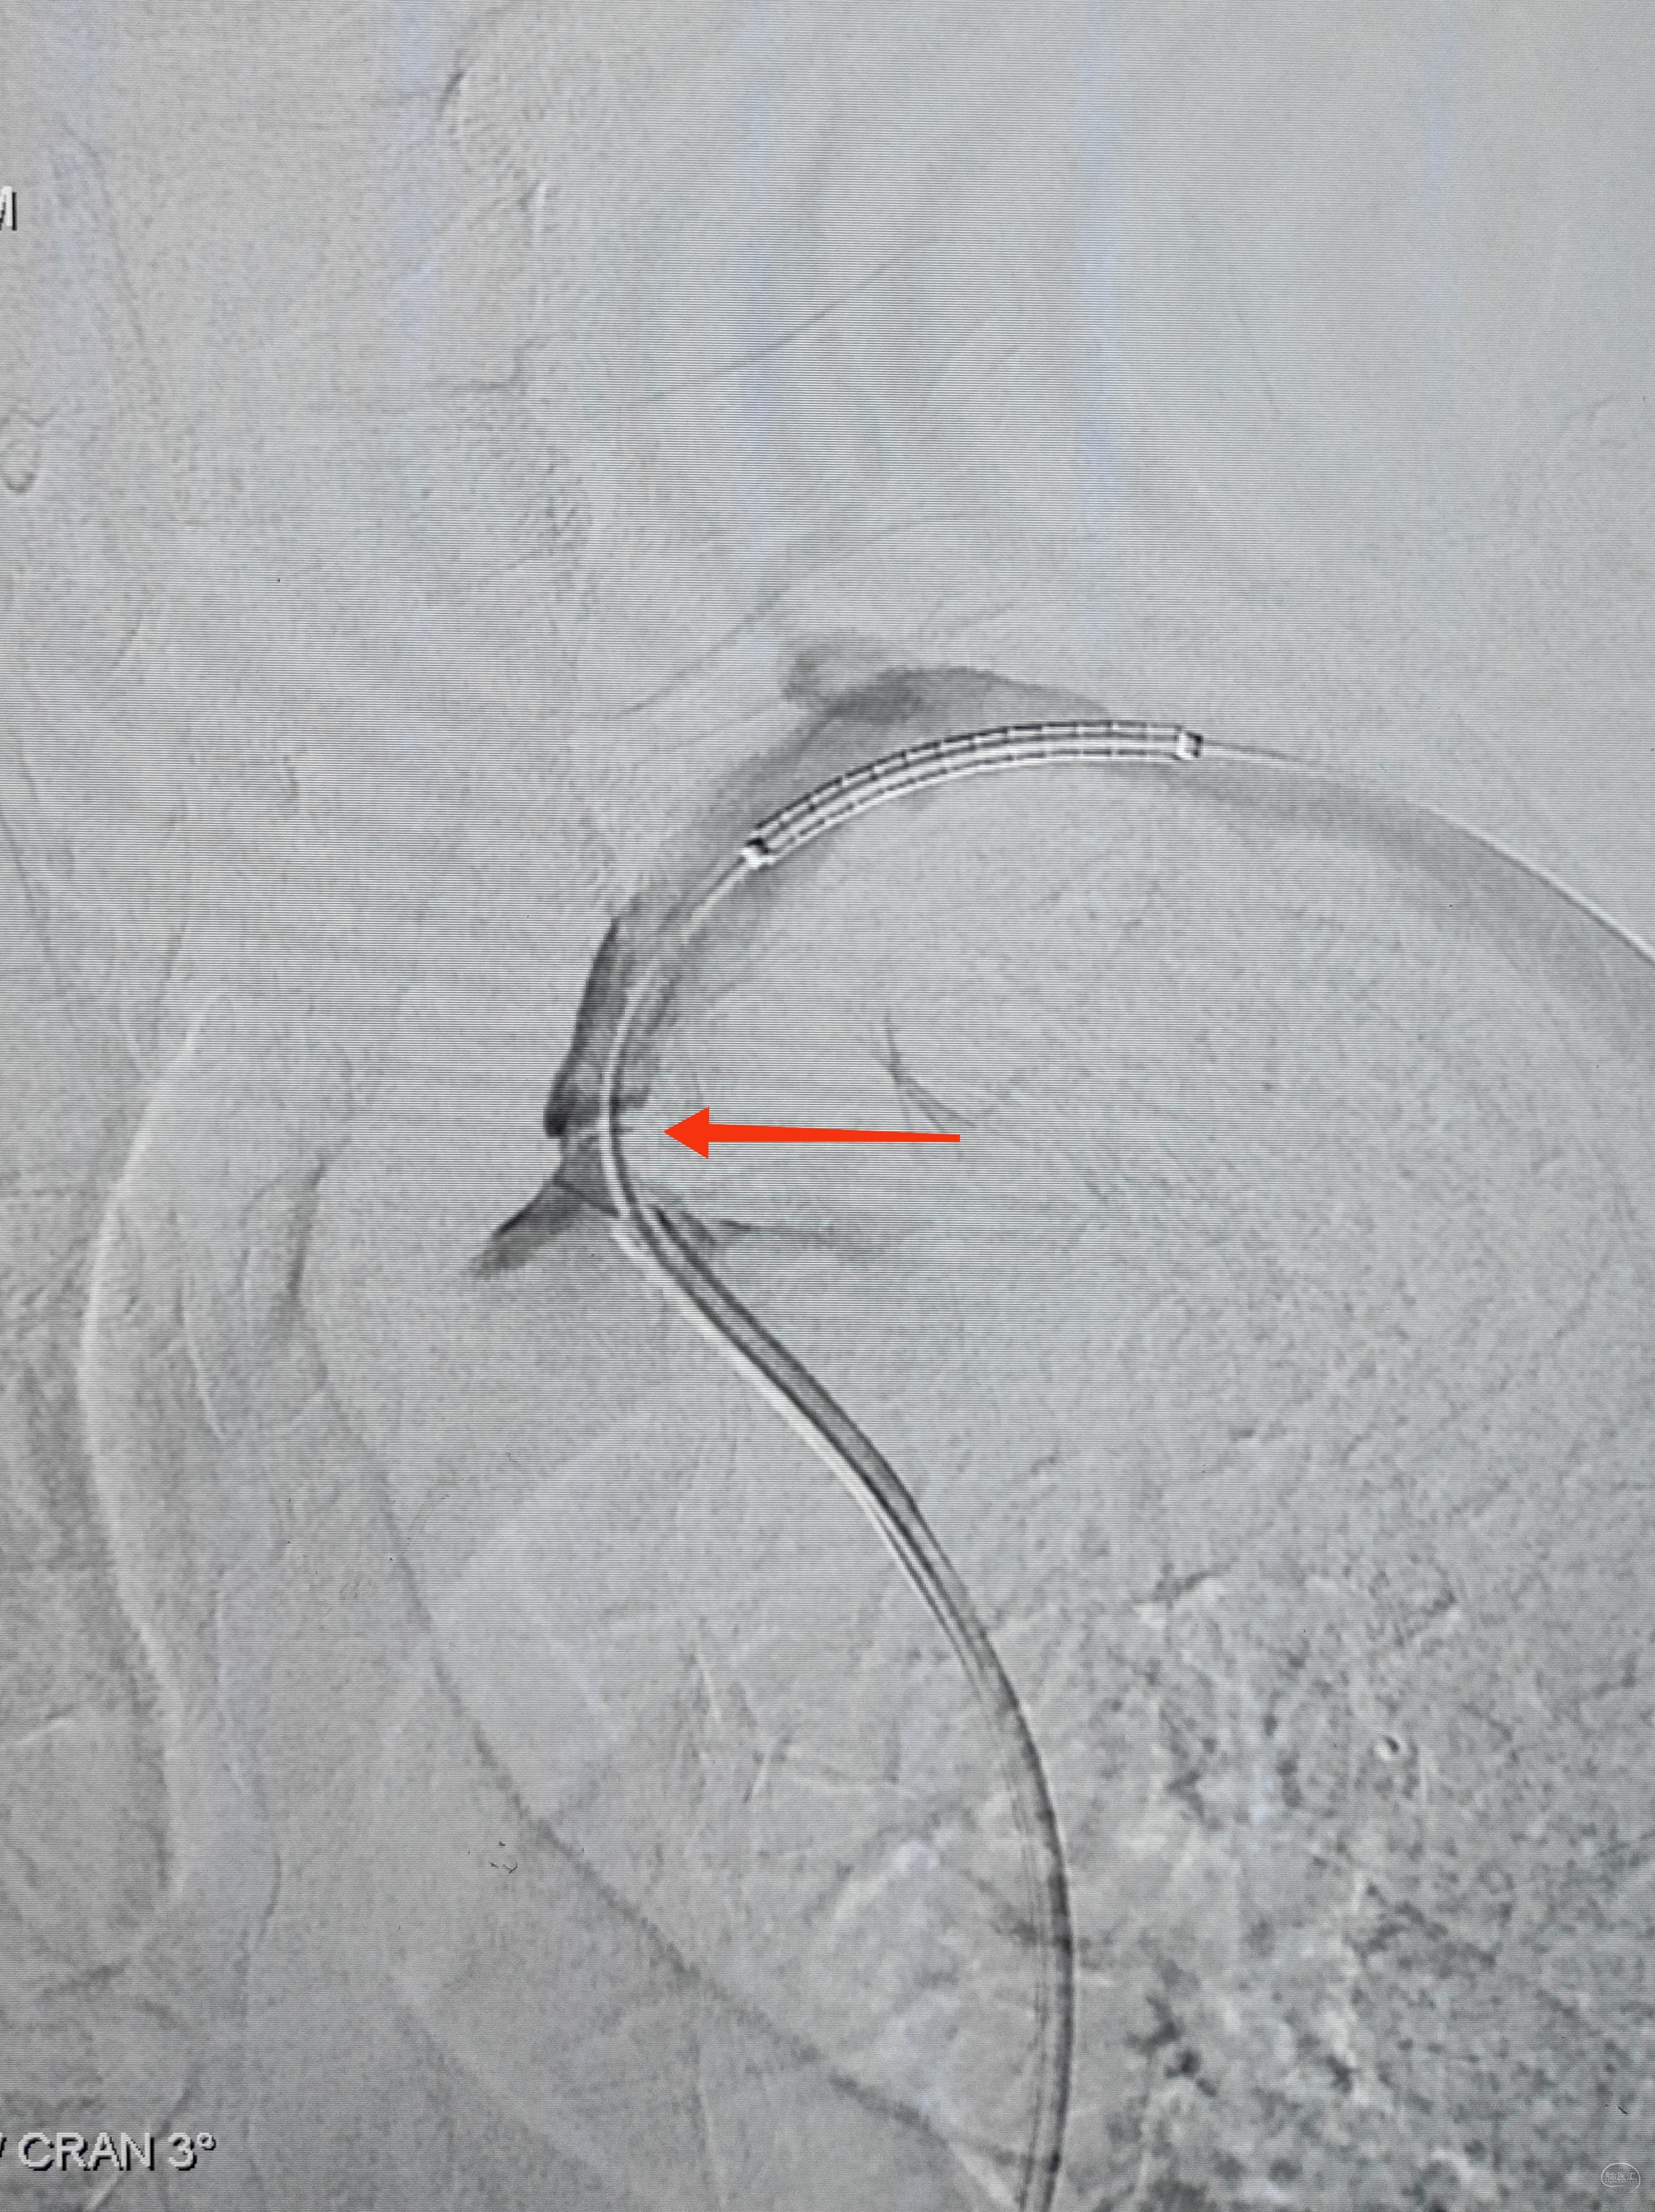

右侧锁骨下造影:右侧椎动脉开口也是重度狭窄,血流速度缓慢,闸门效应明显,此刻,不禁感叹血管的伟大,自己都狭窄得不要不要的了,还努力给对侧代偿供血,奉献精神佳!

因为是极重度狭窄,支架前拟小球囊预扩,谨慎起见,置入泰杰Proender保护伞并打开,以免不测

梯度预扩,先雅培1.5×15小球囊预扩

再Sino3×20球囊预扩

预扩满意,保护伞不浪费,借助保护伞的支撑和保护作用,上送导引导管(不怕掉斑块,物尽其用),为颅内狭窄处理提供更佳支撑